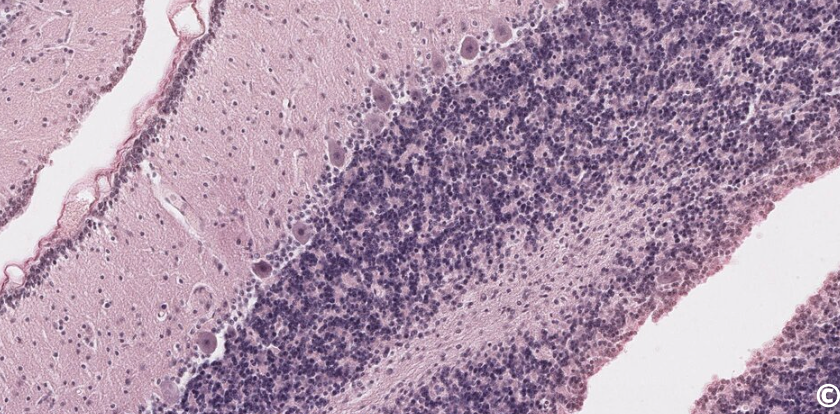

<p>label cells of the cerebellum</p>

label cells of the cerebellum

knowt flashcard image